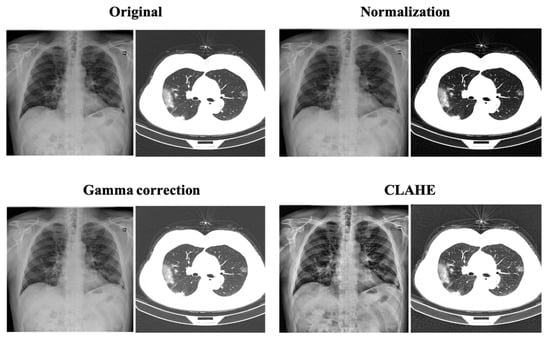

2.2. Image Enhancement Techniques

2.2.1. Normalization

2.2.2. Gamma Correction

2.2.3. Contrast-Limited Adaptive Histogram Equalization